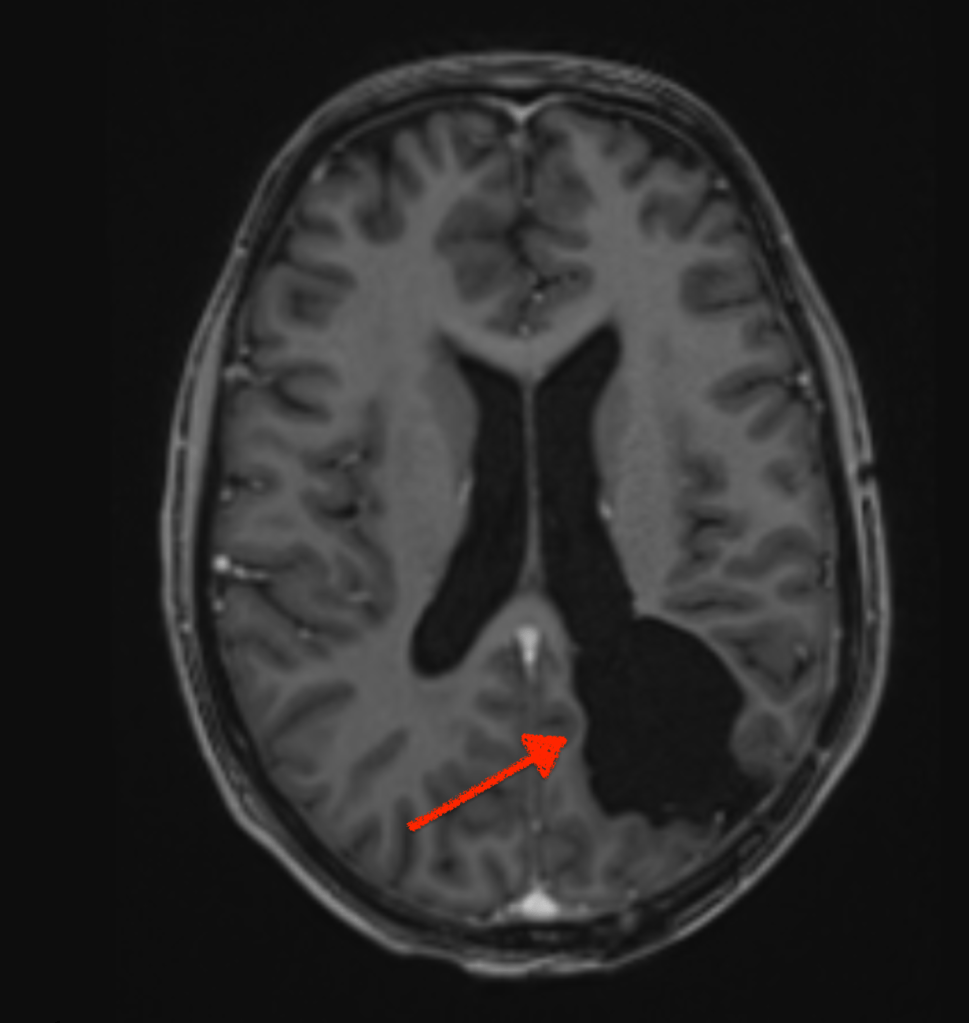

Zoë and only Zoë (as one of her oncologists reminded me) can decide. My role as advocate is to research treatments, make flow charts and advise her. She can, of course take advice from others; I guess doctors would be a good start. Sometimes, I have lost sight of her ability to make the right decision for herself; maybe focusing on the fact that she has had two chunks of her brain removed and acquired a brain injury in the process. Shocking as these images are, the surgeon may have removed the neurons that processes her right peripheral vision; but not her ability to make a decision. The brain is a fascinating organ.